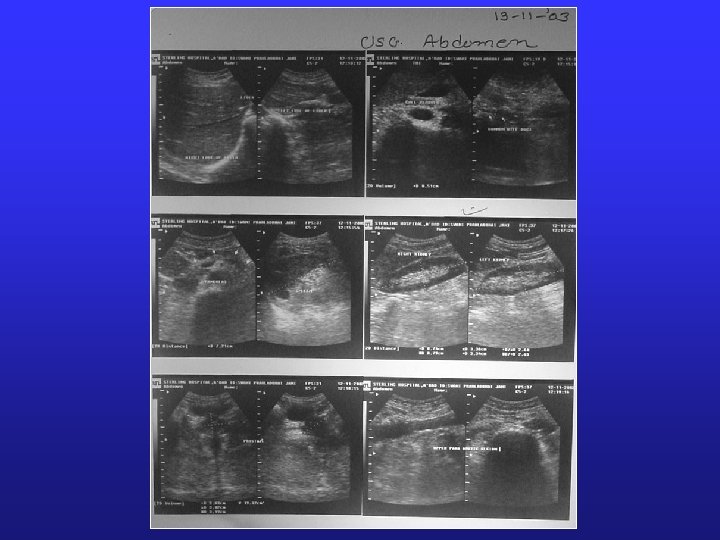

Radiological Investigations § X-Ray Chest PA (12/11/03): No significant abnormality detected. § USG Abdomen (12/11/03): No significant abnormality detected. § Doppler examination of carotid, vertebral, abdominal aorta and peripheral arterial system of lower limbs were quite normal. § MRI of Brain, Neck & abdomen was unremarkable. § MR Angio of Brain. § MR Oesophagus: Normal study § MR cholanigopancreatography: Normal study § MRI Abdomen – pelvis : Presence of bowel gas, etc were seen. Gall bladder collapsed. Urinary bladder partially filled with urine around 70 ml.

USG Kidneys